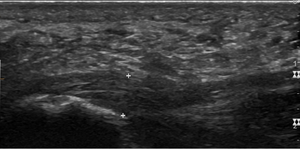

تحتوي اللفافة الأخمصية على ثلاث لفافات - اللفافة المركزية وهي الأثخن بسُمك 4 مم، واللفافة الجانبية بسُمك 2 مم، واللفافة الإنسية بسُمك أقل من 1 مم.[19] نظرياً، يصبح التهاب اللفافة الأخمصية أكثر احتمالًا مع زيادة سماكة اللفافة الأخمصية عند المدخل العقبي. قد يكون مفيداً في التشخيص التصوير بالموجات فوق الصوتية عند سمك يزيد عن 4.5 مم والتصوير بالرنين المغناطيسي عند سمك 4 مم.[20] نتائج التصوير الأخرى، مثل تحديد سماكة اللفافة الأخمصية، غير محددة ولها فائدة محدودة في تشخيص التهاب اللفافة الأخمصية.[13]

عادةً ما يتم تشخيص التهاب اللفافة الأخمصية بواسطة مقدم الرعاية الصحية بعد النظر في التاريخ المرضي للحالة وعوامل الخطر والفحص السريري.[4][17][18] أثناء الفحص البدني قد يؤدي تحسس الجانب الداخلي لعظم العقب وصولاً إلى أخمص القدم إلى الشعور بالألم.[4][11] قد تكون القدم مصابة بعظف ظهري محدود بسبب الشد المفرط في عضلات الساق أو الوتر العقبي.[7] قد يؤدي العطف الظهري للقدم إلى الشعور بالألم بسبب شد اللفافة الأخمصية بهذه الحركة.[4][12] لا تكون دراسات التصوير التشخيصي ضرورية عادةً لتشخيص التهاب اللفافة الأخمصية.[7] أحياناً، قد يقرر الطبيب إجراء دراسات التصوير (مثل الأشعة السينية، الموجات فوق الصوتية التشخيصية، أو التصوير بالرنين المغناطيسي) لاستبعاد الأسباب الخطيرة لألم القدم.